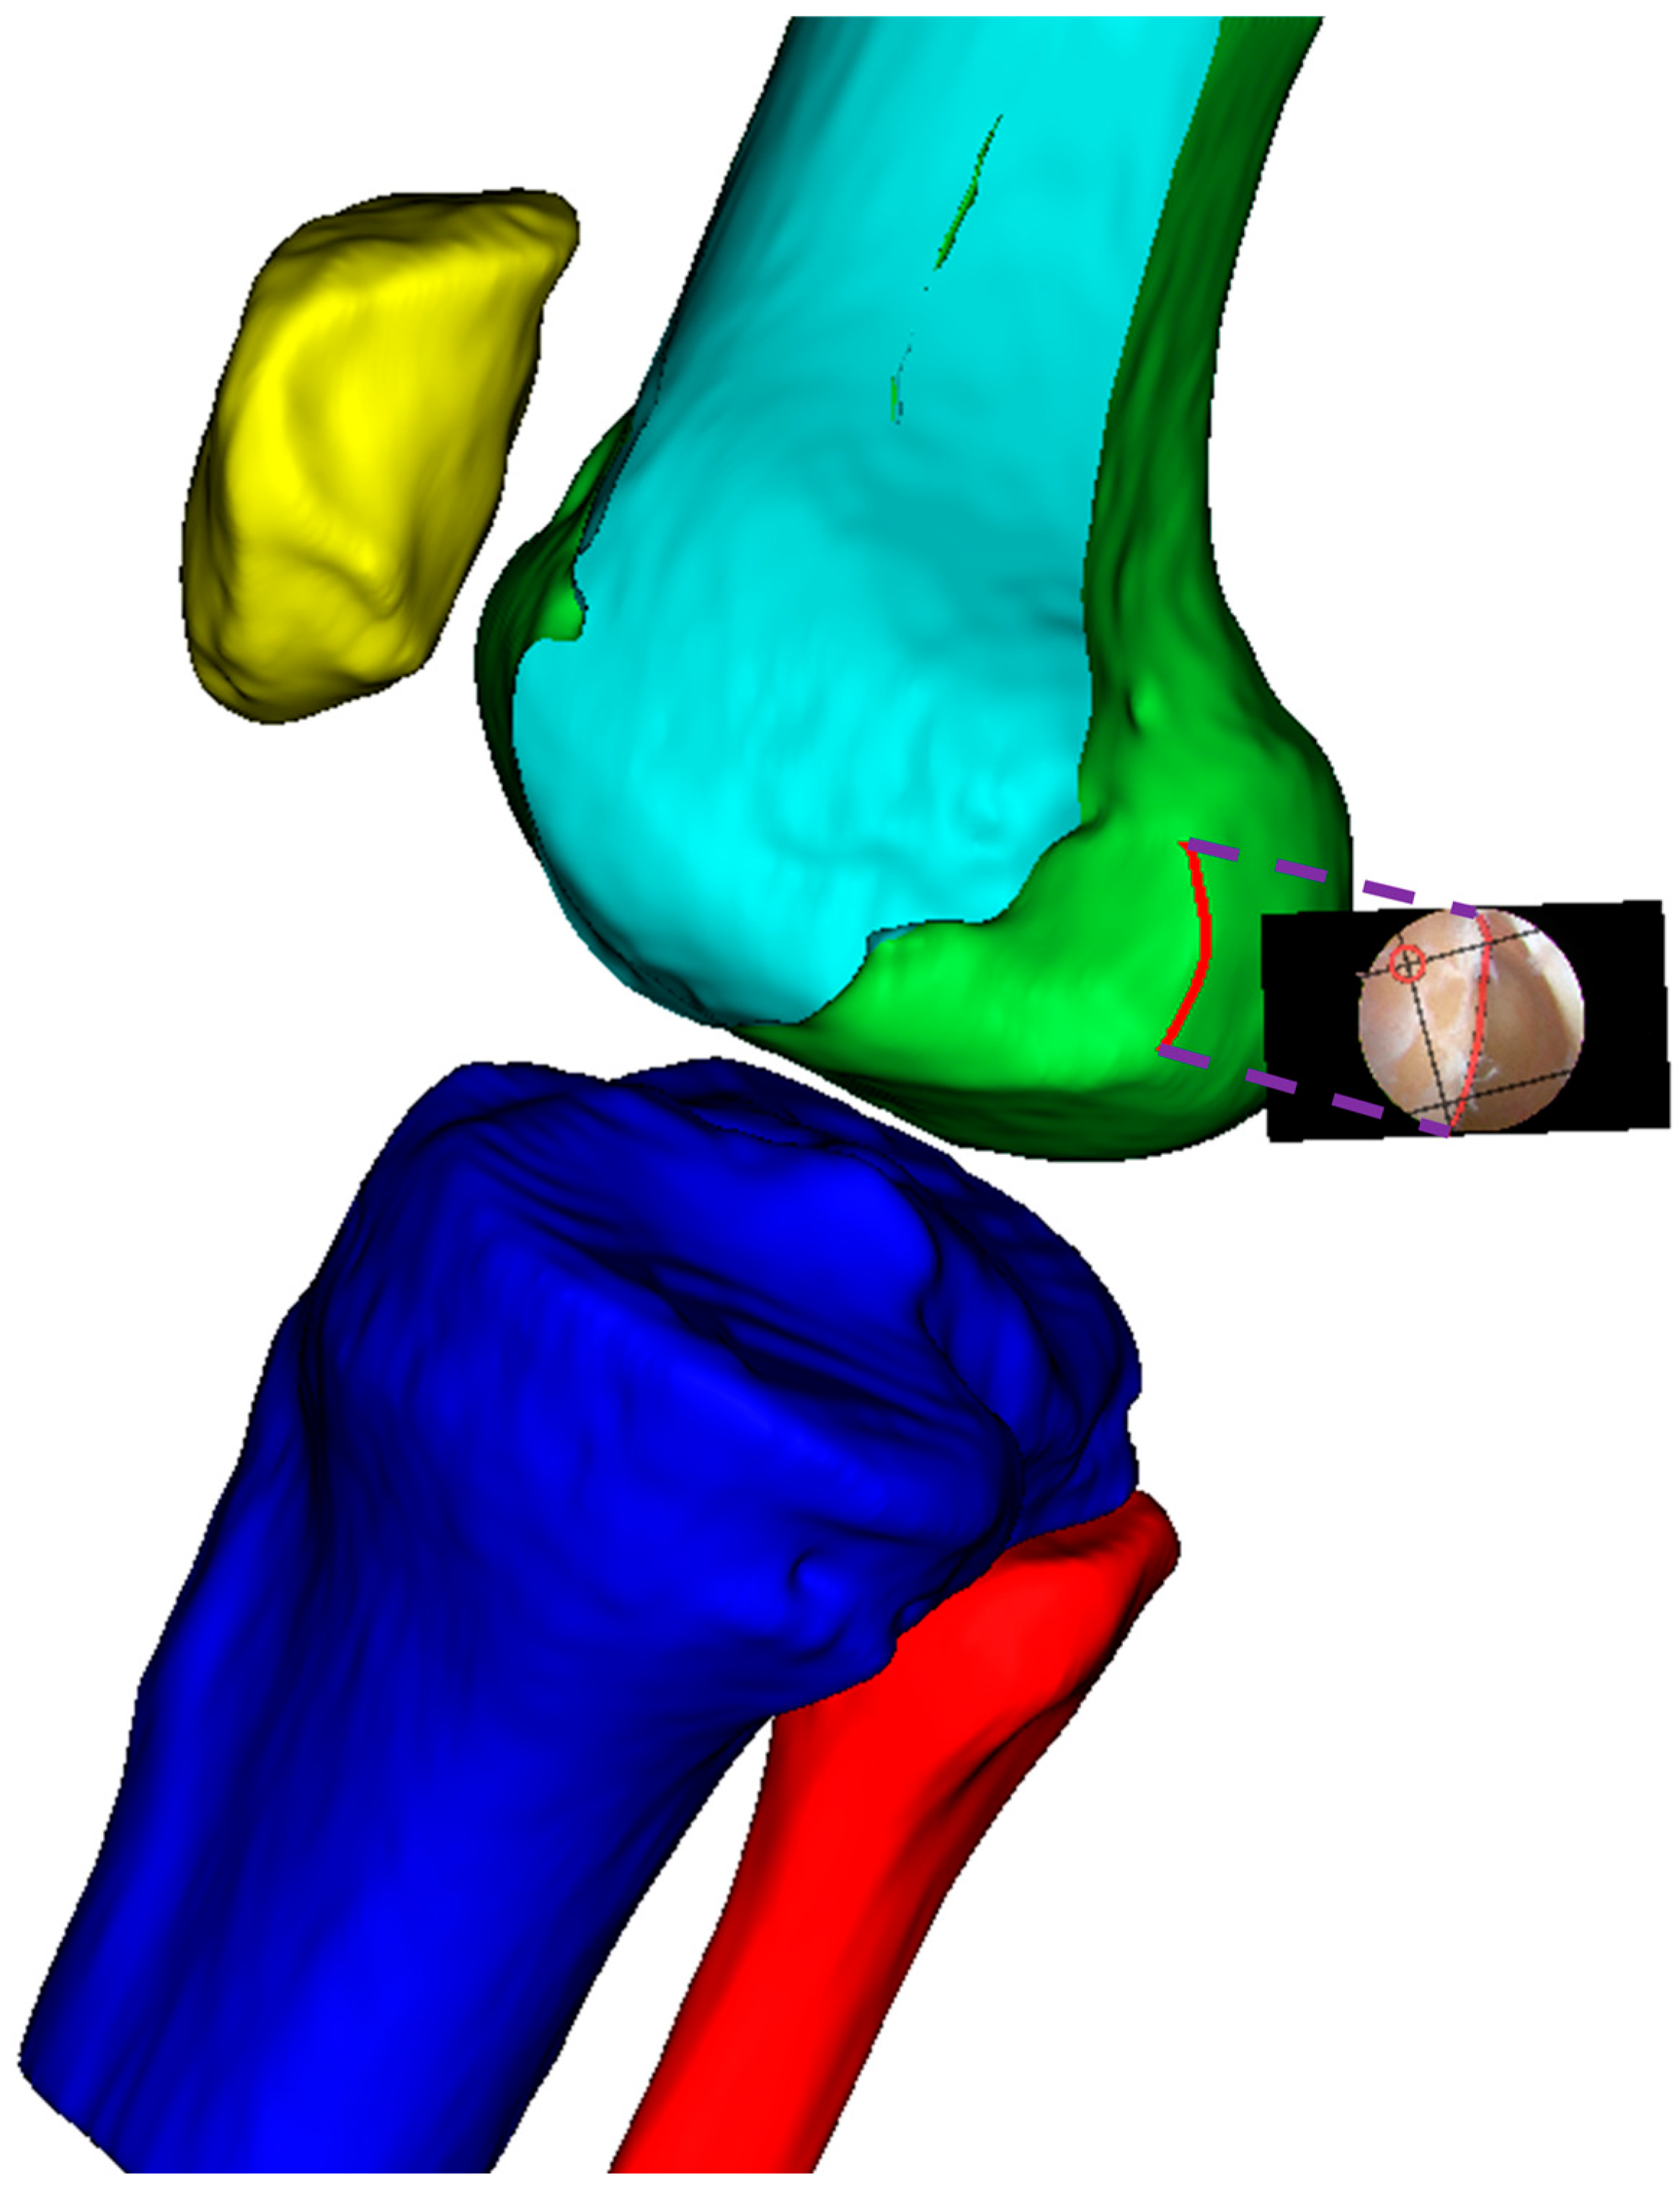

The proposed computer-assisted navigation system consists of two primary components: a three-dimensional femoral model analysis module and an arthroscopic navigation module, working together to provide precise guidance during ACLR procedures (as shown in Figure 1). The workflow encompasses three phases, preoperative processing, anatomical feature extraction, and real-time navigation.

2.2. 3D Femoral Model Processing

The processing of the three-dimensional femoral model consists of two essential steps, reconstruction of the distal femoral surface model and establishment of the initial sagittal plane. Starting with high-resolution CT data of the patient’s knee (slice thickness 1 mm, pixel spacing 0.5 mm), the system first reconstructs the three-dimensional surface model of the distal femur, as shown in Figure 2. This reconstruction process utilizes threshold-based segmentation that takes advantage of the natural contrast between bone and surrounding tissues in CT images, followed by morphological operations to refine the initial segmentation. The resulting volumetric data are then converted into a surface mesh model through a marching cubes algorithm, producing a detailed representation of the distal femoral surface.

Figure 2. Three-dimensional surface model reconstruction of the distal femur from CT images.